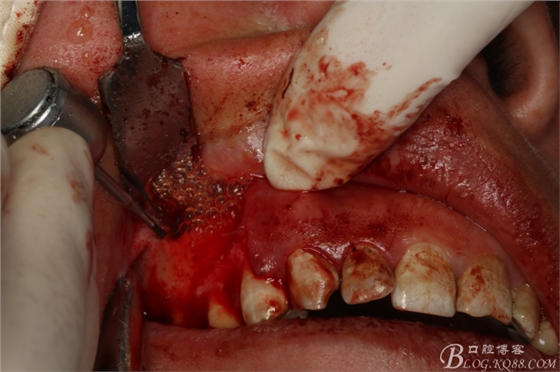

圖15.搔刮頰側(cè)牙根周?chē)∽兘M織

圖16.搔刮干凈16根尖區(qū)囊腔

圖17.囊腔填塞膠原蛋白海綿